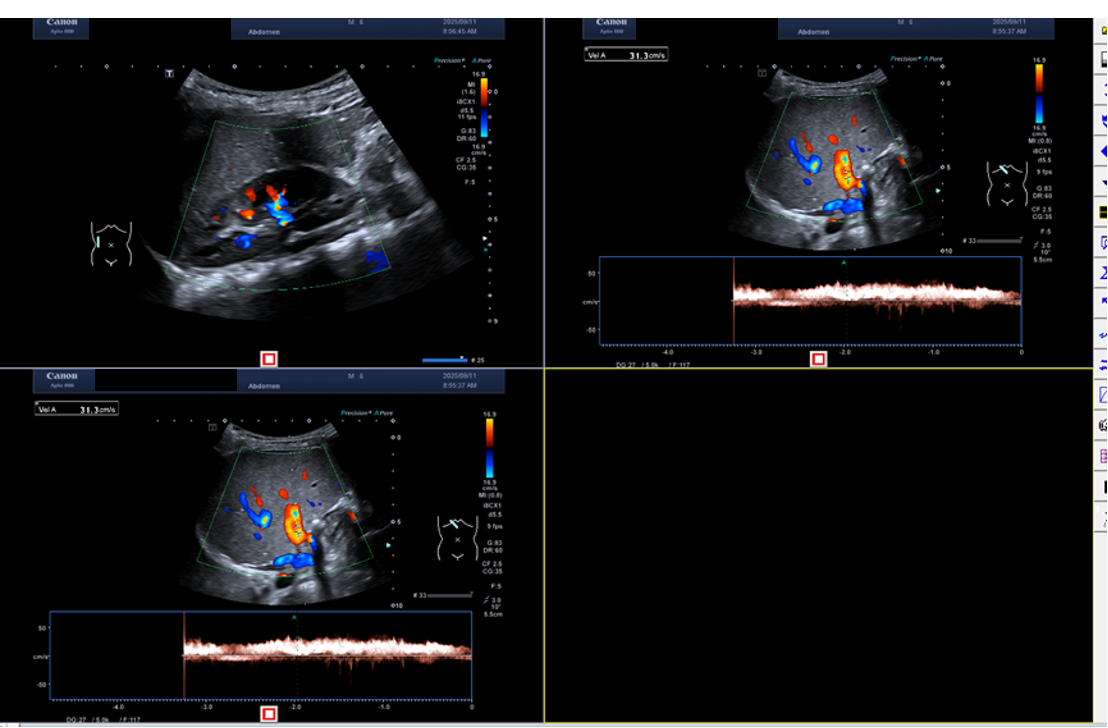

2025.08.28

腹部超声:未见明显异常和占位性病变。